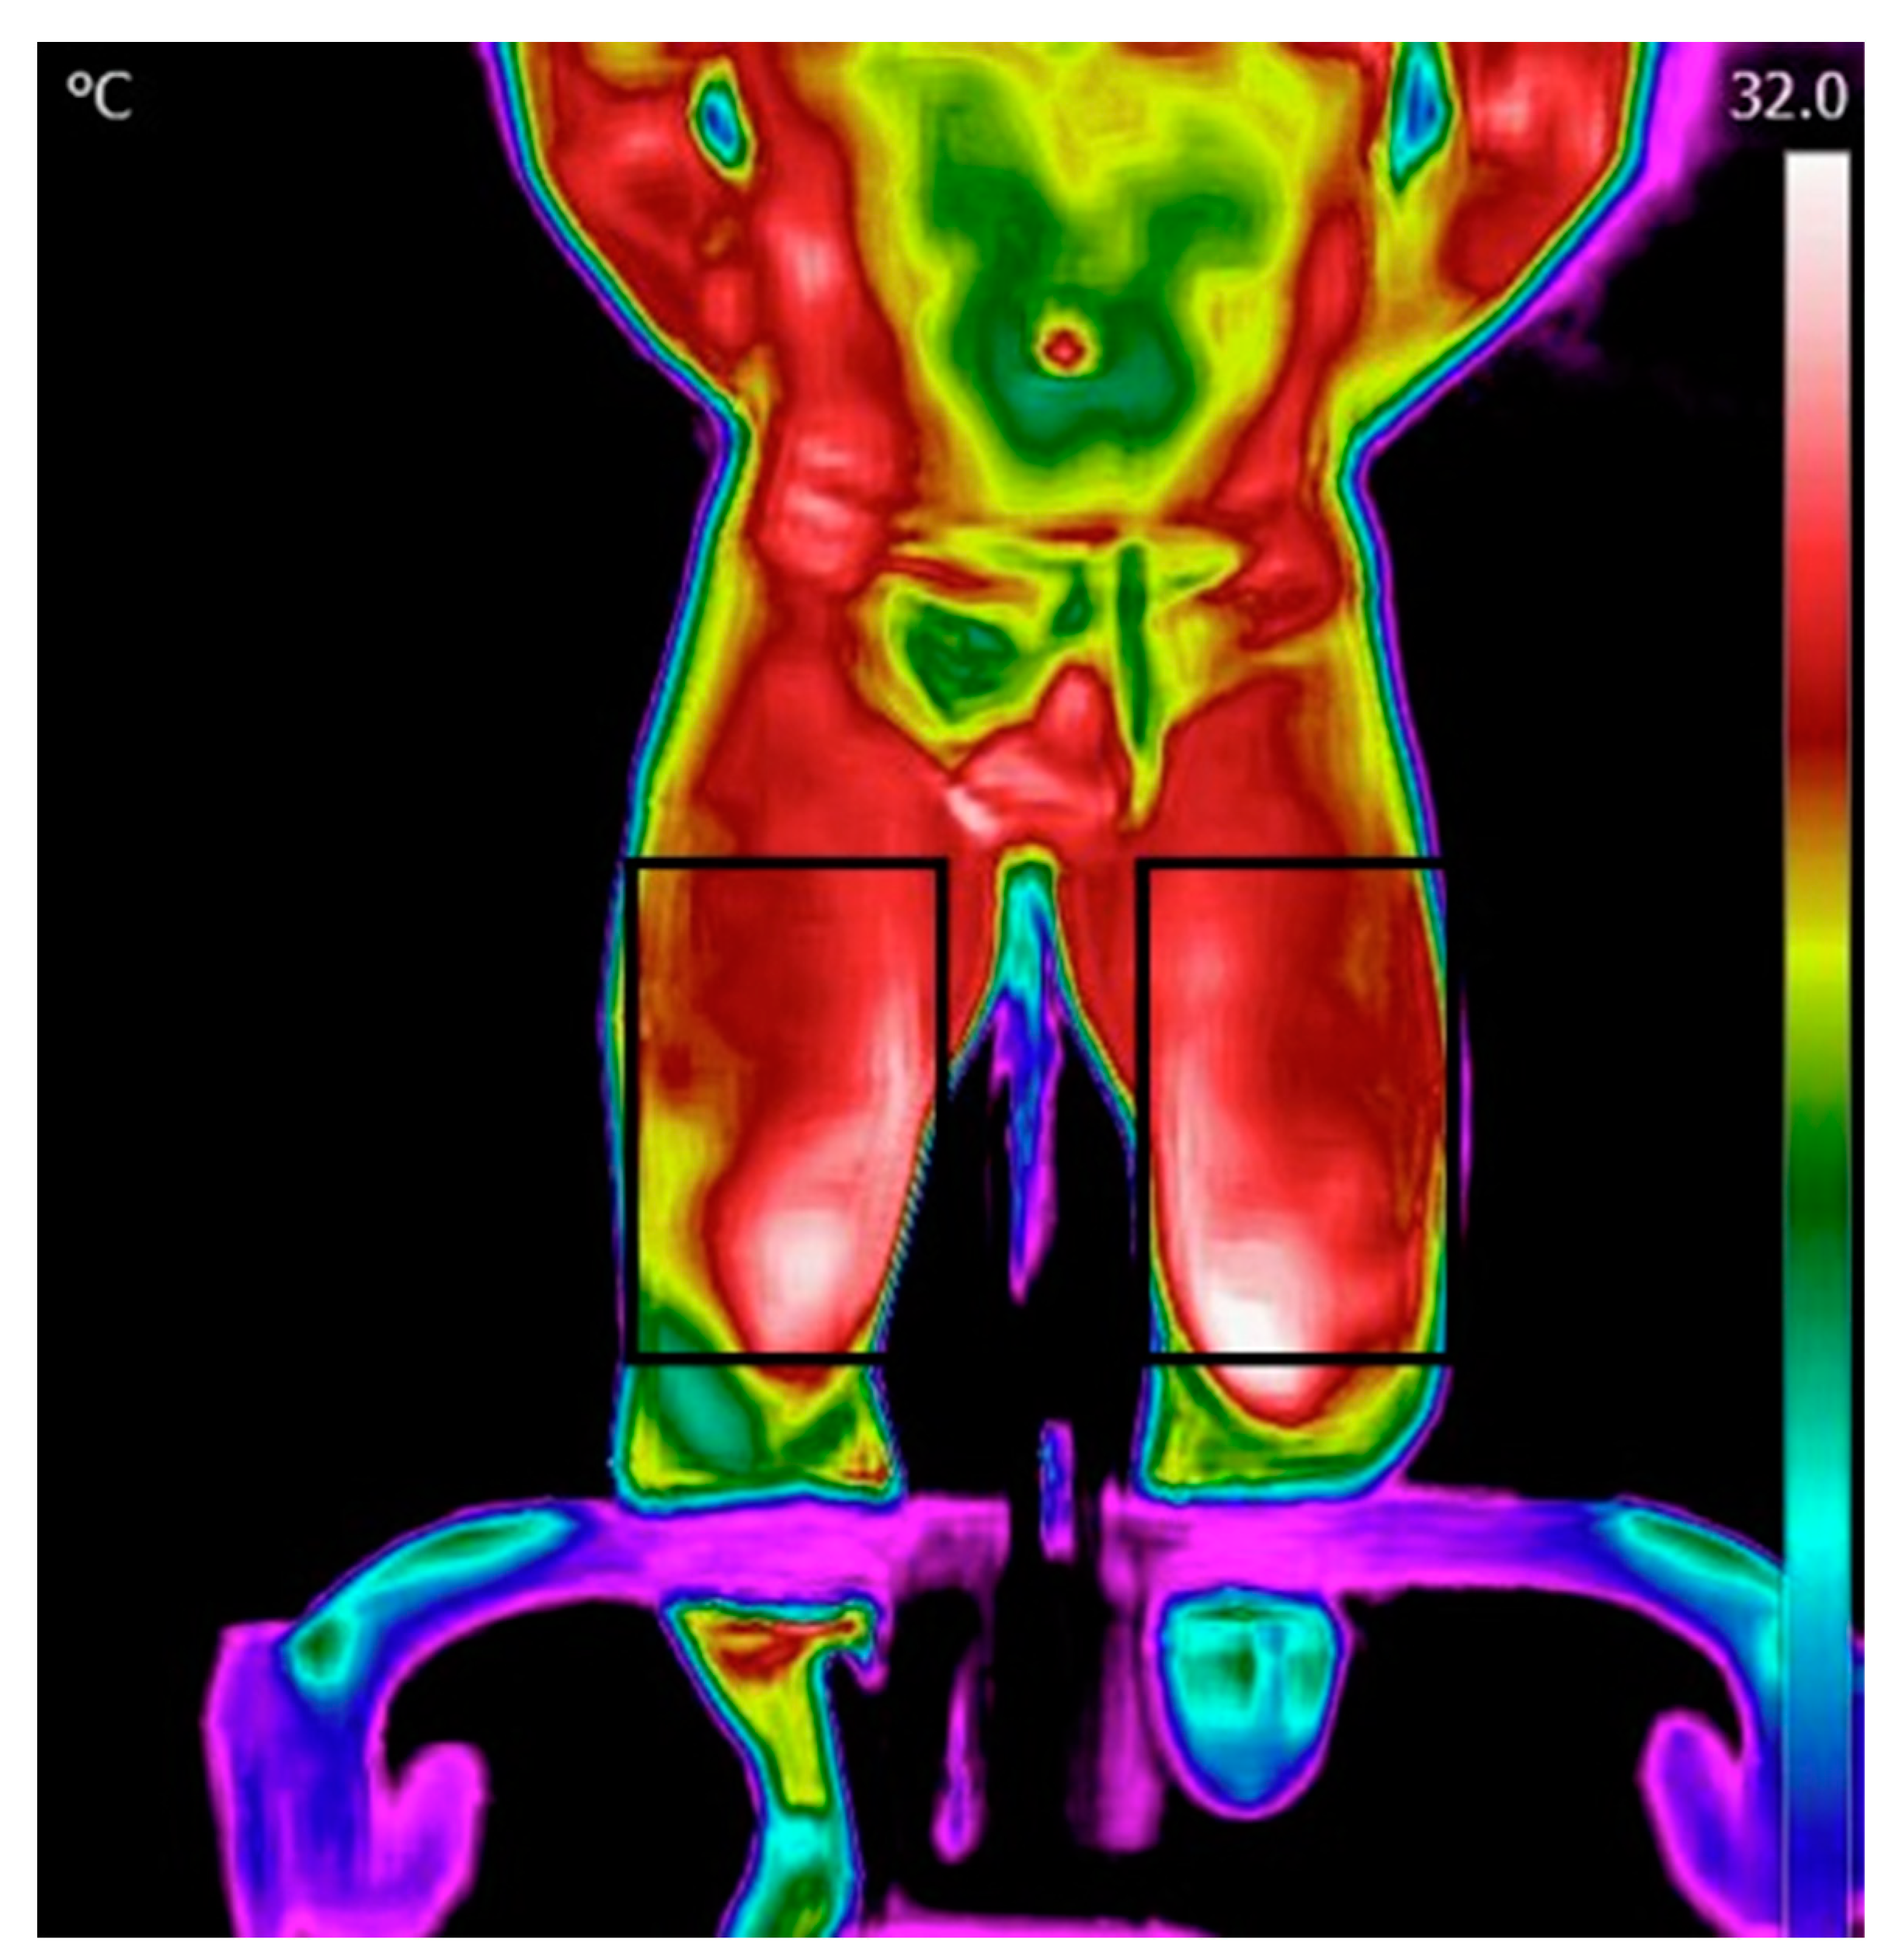

Processing and analysis of the images were performed using the FLIR Tools application. The data was then transferred into Excel and thereafter processed using MATLAB. The initial step involved reading a matrix containing temperature values within the region of interest (ROI). Thereafter, the temperature map was displayed, and an ROI was manually selected for the forehead, chest, and legs (Figure 2). Subsequently, the algorithm computed the mean and maximum temperature in each ROI.

Figure 3 shows representative thermal images during different stages of this study. Chest temperature was observed to increase after the test but decrease during recovery, while leg temperature continued to increase during the recovery period.

Figure 3. Representative thermal images. The chest region of interest (ROI): (A) before the test; (B) after the test; and (C) after 15 min of recovery. The leg ROIs: (D) before the test; (E) after the test; and (F) after 15 min of recovery.